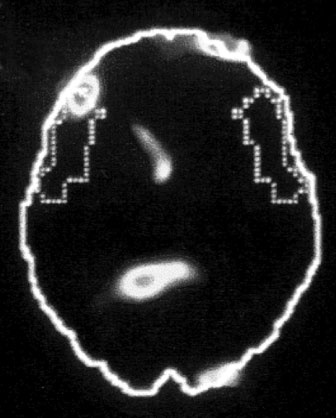

А. Правая лимбическая область

Иллюстрация к книге — Тело помнит все [i_002.jpg]

Изображение мозга в процессе переживания травмы. Светлые пятна в лимбической коре (А) и зрительной коре (Б) соответствуют повышенной активности мозга в этих участках. На снимке (В) видна значительно пониженная активность речевого центра мозга.

Когда через эту процедуру прошли все восемь участников, Скотт Рауч вместе со своими математиками и статистиками взялся за создание составного снимка, по которому можно было бы наглядно сравнить активность мозга в нейтральном состоянии и в момент появления неприятных воспоминаний. Несколько недель спустя он отправил мне результаты, которые вы видите выше. Я приклеил эти снимки на дверцу своего холодильника в кухне и на протяжении следующих нескольких месяцев каждый вечер их разглядывал. Должно быть, именно так чувствовали себя первые астрономы, взглянув через телескоп на неизученное звездное скопление.

На снимках были некоторые сбивающие с толку точки и цвета, однако самая яркая область активации мозга – большое красное пятно в правом нижнем центре мозга, известном как лимбическая область, или эмоциональный мозг, – никакого удивления не вызывала. Мы уже знали, что сильные эмоции активируют лимбическую систему, в особенности участок внутри нее, известный как миндалевидное тело.